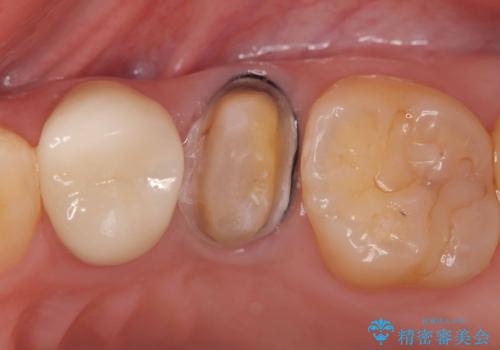

- 「銀歯があるとお口の中が気持ち悪い感じがするので、セラミックに変えたい」を主訴に来院された患者様です。

銀歯と虫歯を除去し、オールセラミッククラウンで治療を行いました。

銀歯の下は虫歯になっていました。 根管治療は希望されなかったため、虫歯を除去後、被せ物のみオールセラミックで治療を行いました。